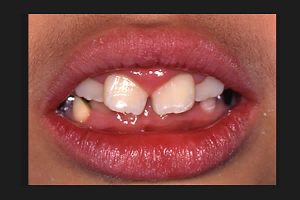

最近、口をポカ~ンとあけている子どもや若者が気になってしかたがない。そんな子どもが以前より増していると思う。口呼吸をしている子どもの口唇は、厚かったり、上唇が山型をしているのですぐわかる。それに、歯肉が硬く腫れている。

(図2)

扁桃腺の腫れ

これも外気のせいである。そこで、幼稚園や小学校で口唇閉鎖力を測ってみた。